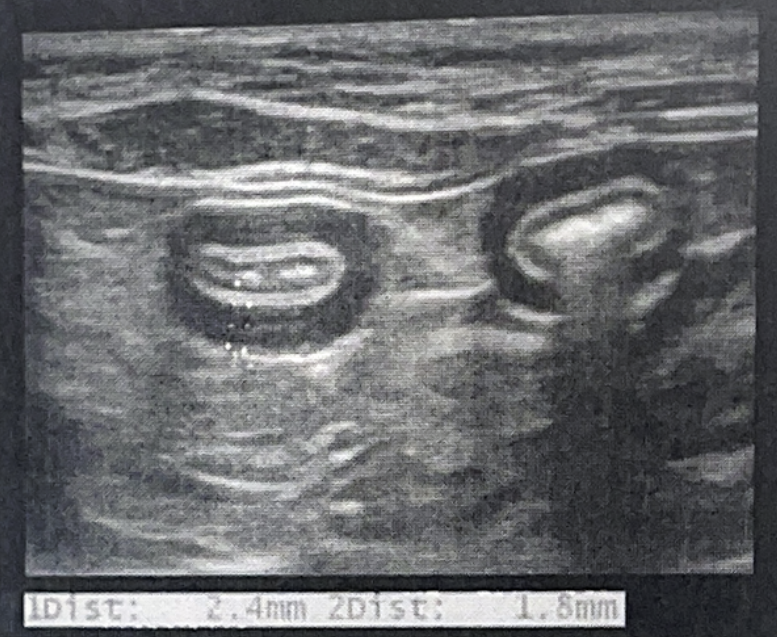

✴️ Choleliths (담석)

Quote

- EHBDD (Extrahepatic bile duct obstruction) 유발

- Acoustic shadowing

- Surface는 매우 밝음 (강한 반사계면)

- Calculi

- 강한 반사계면, 아래로 acoustic shadowing